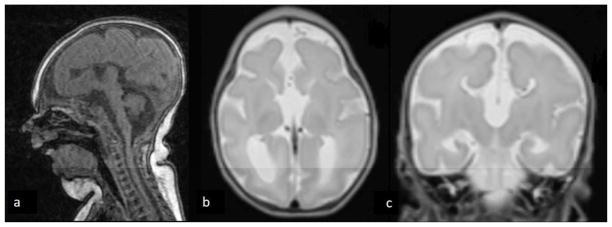

Functional characterization of biallelic RTTN variants identified in an infant with microcephaly, simplified gyral pattern, pontocerebellar hypoplasia, and seizures.

Biallelic deleterious variants in RTTN, which encodes rotatin, are associated with primary microcephaly, polymicrogyria, seizures, intellectual disability, and primordial dwarfism in human infants.

We performed exome sequencing of an infant with primary microcephaly, pontocerebellar hypoplasia, and intractable seizures and his healthy, unrelated parents. We cultured the infant's fibroblasts to determine primary ciliary phenotype.

We identified biallelic variants in RTTN in the affected infant: a novel missense variant and a rare, intronic variant that results in aberrant transcript splicing. Cultured fibroblasts from the infant demonstrated reduced length and number of primary cilia.

Biallelic variants in RTTN cause primary microcephaly in infants. Functional characterization of primary cilia length and number can be used to determine pathogenicity of RTTN variants.